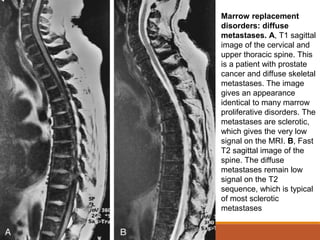

Marrow replacement

disorders: diffuse

metastases. A, T1 sagittal

image of the cervical and

upper thoracic spine. This

is a patient with prostate

cancer and diffuse skeletal

metastases. The image

gives an appearance

identical to many marrow

proliferative disorders. The

metastases are sclerotic,

which gives the very low

signal on the MRI. B, Fast

T2 sagittal image of the

spine. The diffuse

metastases remain low

signal on the T2

sequence, which is typical

of most sclerotic

metastases